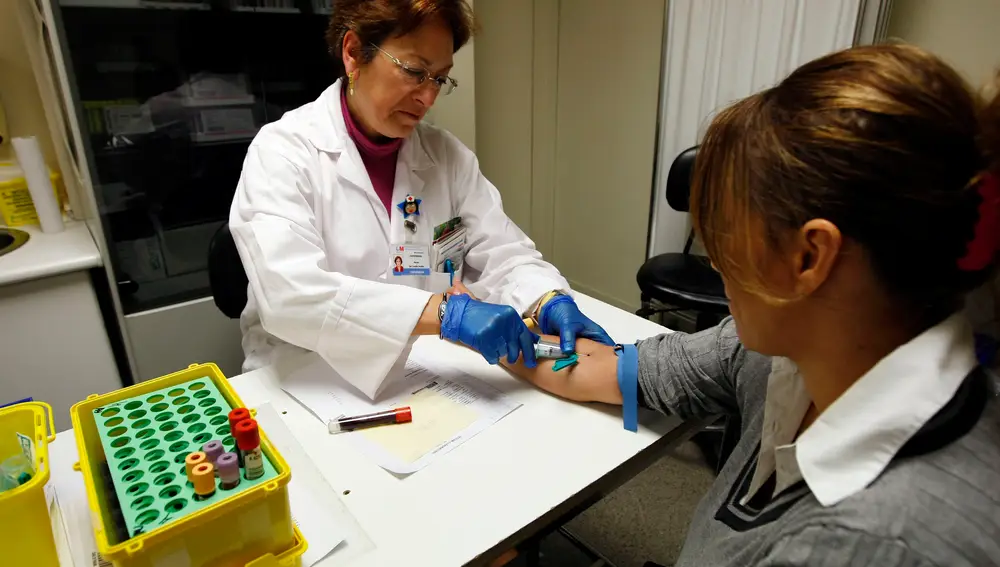

Superando el miedo a la sangre: tratamientos efectivos para la hematofobia

Como ya hemos explicado con anterioridad, esta fobia es una de las más comunes. De hecho, se estima que hasta a un 4% de la población podría padecer esta fobia en mayor o menor grado, siendo mucho más prevalente en mujeres que en hombres. Básicamente, la hematofobia consiste en un miedo extremo a la sangre, las agujas y las heridas abiertas.

Algo que ocurre en el caso particular de la hematofobia, y que ocurre de forma contraria en el resto de fobias, es que en los afectados por la hemofobia el ritmo cardiaco no sólo no aumenta, sino que disminuye. El brusco descenso de la presión arterial disminuye la cantidad de sangre que llega al cerebro, lo que provoca -a su vez- el mareo. En muchos casos, el ritmo cardiaco de los afectados por la hemofobia disminuye tanto… que puede derivar -incluso- en el desmayo. Es un fenómeno para el que todavía no existe una explicación definitiva y absolutamente aceptada.